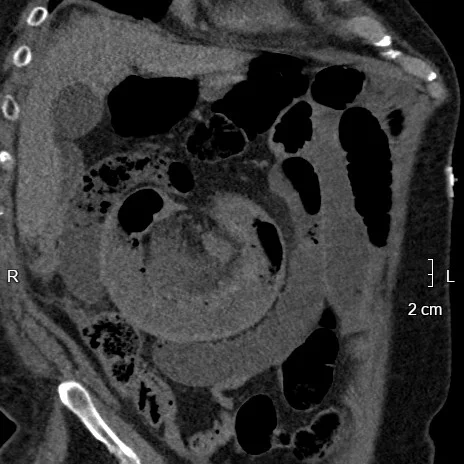

83 y.o. male with ischemic cardiomyopathy (EF 38%), CAD, chronic kidney disease (stage 3), aortic stenosis s/p TAVR admitted for abdominal pain, nausea and vomiting. Estimated GFR 43 mL/min/1.73 m2 BSA. CT angiogram of the abdomen with reduced contrast load, requested after radiologist and physician consultation.

Scan performed with 60 mL injection at 4 mL/sec, using 50% contrast (30 mL contrast load). Mesenteric vasculature is patent. Diffusely dilated loops of small bowel, with a focal cluster of  hyperdense loops with engorged mesentery in the right upper quadrant in a radial configuration. A closed loop obstruction was called, and patient taken to the OR urgently.

Is the hyperdense closed loop inflamed, or is it something else? On spectral analysis, virtual non-contrast shows bowel wall in the closed loop remains hyperdense, suggestive of hemorrhage. There is no iodine uptake in the closed loop. On surgery, a 20 cm closed loop "black, purple, and necrotic appearing" was found. Bowel resection and primary anastomosis was performed. Path confirms a completely necrotic loop with transmural hemorrhage

Spectral CT can help with "imaging 3.0". The exam was done is a safer fashion, after radiologist consultation, using a lowed dose of iodinated contrast. Virtual non-contrast eliminates the need for a true non-contrast phase, reducing radiation dose (admittedly, not of primary importance in a 83 year old, but the principle stands). The combination of virtual non-contrast and iodine map (even with reduced contrast load) enables a prompt diagnosis of closed loop obstruction with hemorrhagic necrosis (truly an actionable report), expediting surgery and correlating beautifully with pathology.

Conventional CT, oblique coronal plane: Closed loop in right abdomen (note the radial arrangement)

Conventional axial image with closed loop in right lower quadrant